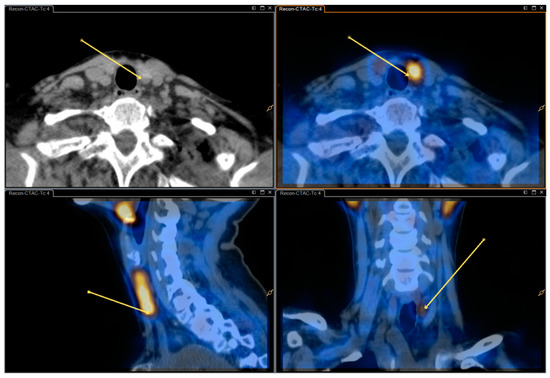

See Figure 1 and Figure 2 for dual/dual and dual/single images.

Figure 2. Single isotope SPECT/CT image (Tc-99m-sestamibi) with and without fusion—same patient as in Figure 1.